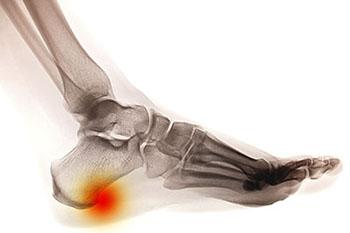

heel spur

Heel spurs are brought upon by a calcium deposit that causes a bony protrusion on the underside of the heel bone. It normally forms over time and can best be diagnosed through an x-ray examination. Heel spurs are commonly linked with plantar fasciitis, an inflammation that runs along the bottom of the foot. Common symptoms of heel spurs include pain towards the affected area, inflammation, and swelling at the front of the heel.

Heel spurs are calcium deposits that produce bony growths on the underside of the heel bone. They may or may not cause heel pain. Heel spurs are typically diagnosed through an X-ray.